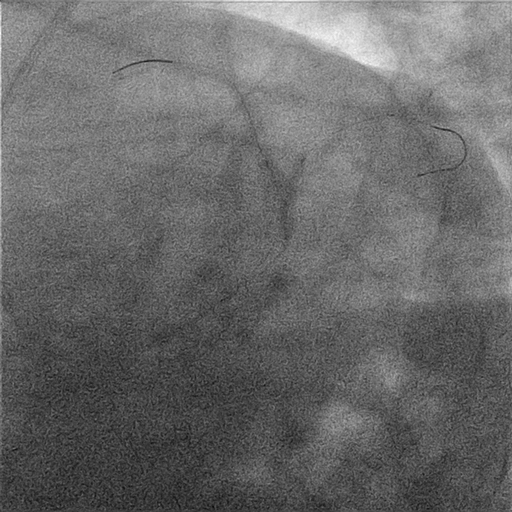

Angiography

LMCA: short, without lesions

LAD: proximal aneurysm (Figure 1) with mild mid and distal lesions; the first diagonal branch had a severe ostial lesion